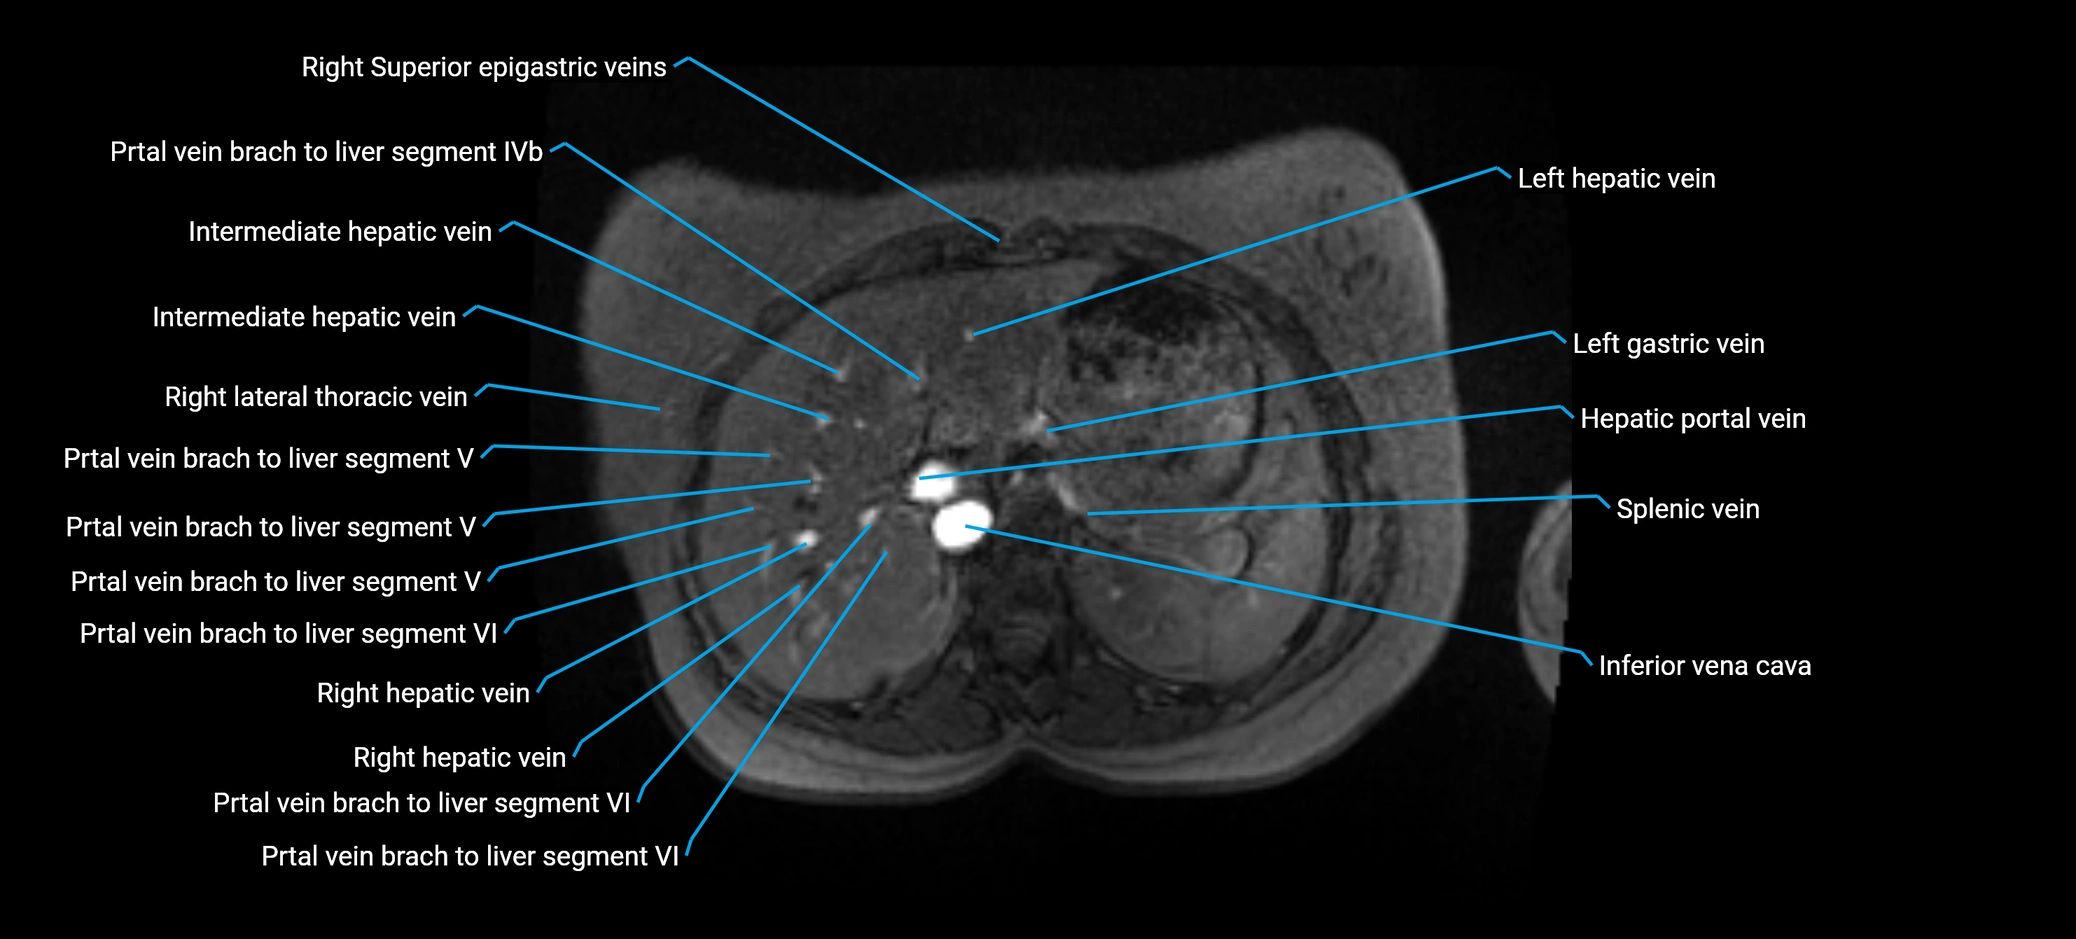

The anterior right branch of the portal vein is a major intrahepatic division of the right portal vein. After the main portal vein bifurcates into right and left branches, the right portal vein divides into anterior and posterior segmental branches.

The anterior right branch supplies the anterolateral liver segments (Segment V) and anteromedial liver segments (Segment VIII) within the right hepatic lobe. It operates as a key vascular route delivering nutrient-rich portal venous blood to the central and superior right liver.

This segmental vasculature is of major importance in hepatic surgery, embolization, segmental resection, transplantation, and imaging-based liver segmentation.

Post-Contrast T1 Fat-Sat GRE:

• Enhances brightly and homogeneously during the portal venous phase

• Clearly delineates branching into segments V and VIII

• Best sequence for evaluating patency, caliber, and anatomic variants

MRI image

image